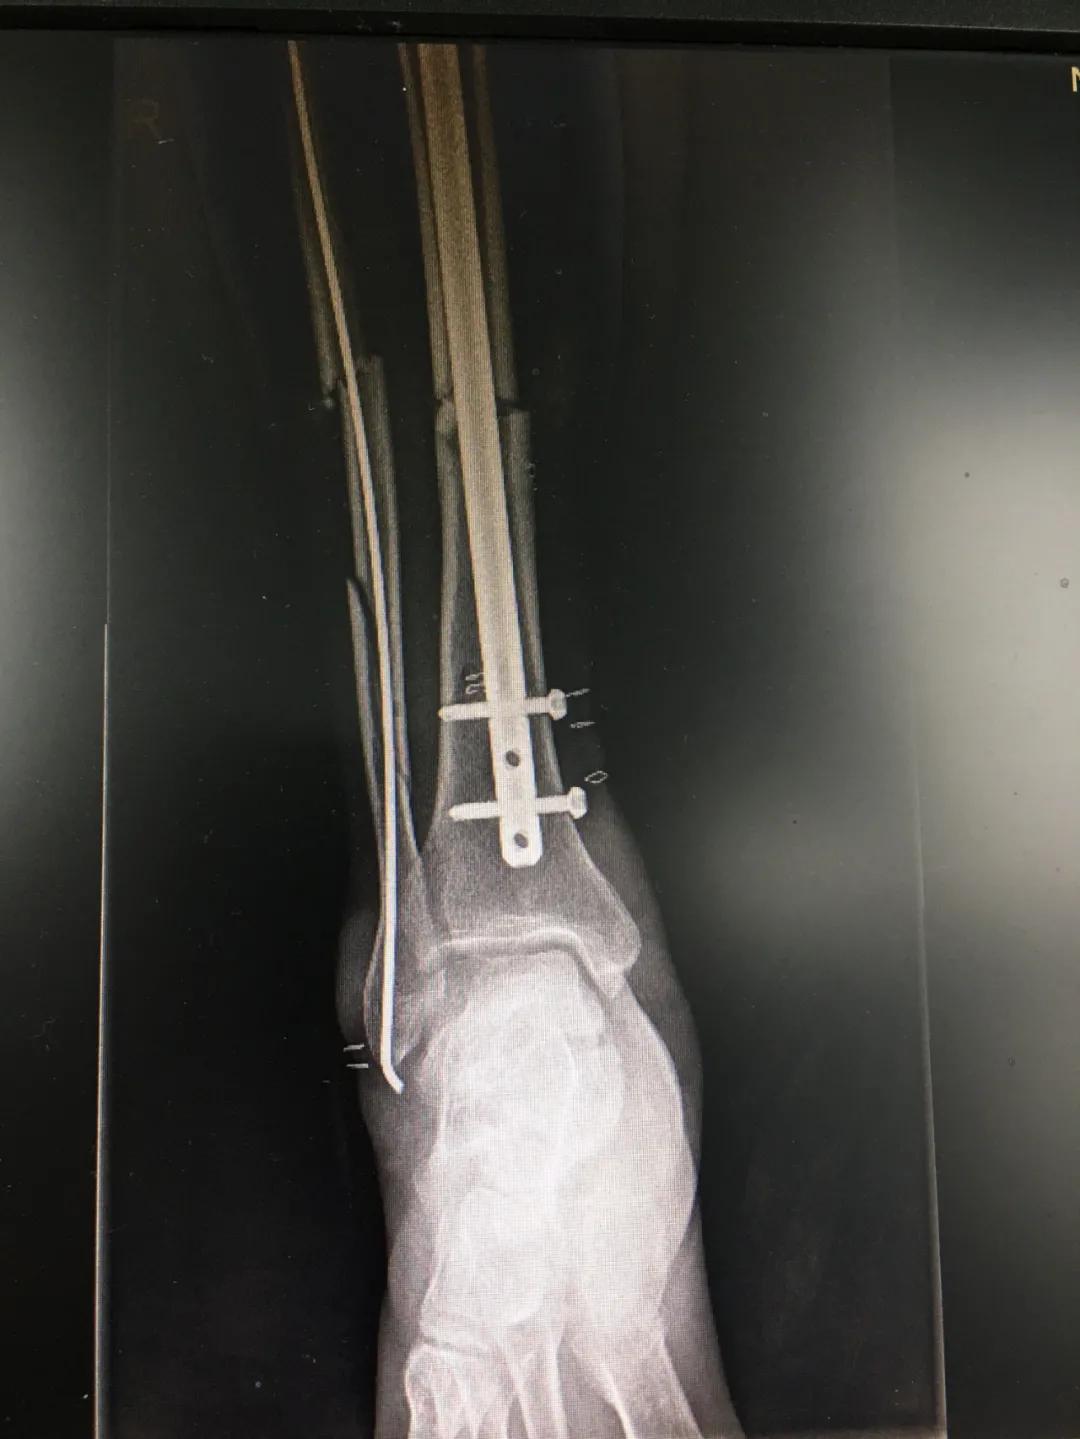

为患者实施的骨折微创复位固定技术是创伤骨科的特色技术。相较传统手术需要20公分的切口,微创手术只需要3公分左右。闭合复位髓内钉固定技术、经皮插板内固定技术(mippo技术)、闭合复位空心螺钉固定技术等一系列的微创复位固定技术,具有切口小、出血少、创伤小、愈合快、疤痕小等优点,骨折术后并发症明显降低,患者还可以早期负重功能锻炼。

另一位患者朱先生因车祸导致了右胫腓骨骨折,同样的小腿三段骨折,实施了微创闭合复位髓内钉固定术后,目前已经逐步进行康复功能锻炼。